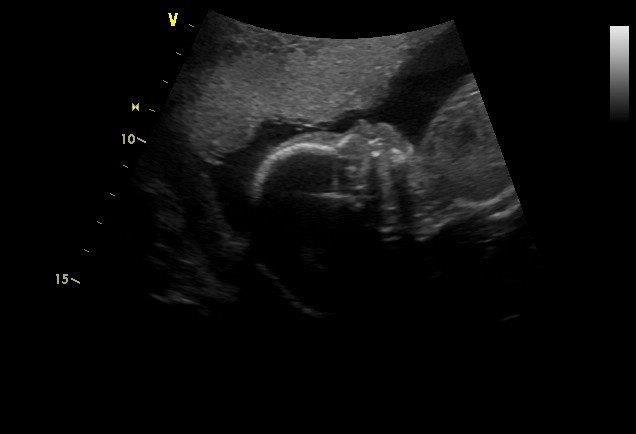

..... tak jsem dnes byla na velkém UZ avše je naštěstí v pořádku, akorát na nás malá absolutně kašlala a zakutala se tam někam tak, že pan dr. nemohl nejdřív pořádně prohlédnout srdíčko, ostatní už jakžtakž měl.....takže mě poslal se chvíli procházet a pak nanovo. Už se to pak podařilo, akorát mám takovou zvláštní fotečku, protože se hrozně mlela a nšlo ji chytit

, takže je tam vidět jen obličejík z profilu a kousek tělíčka. Nemá ráda doktory....to bude mít po tatínkovi